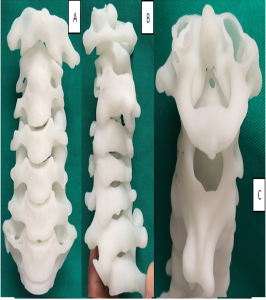

- Η κατασκευή τμημάτων της Σπονδυλικής Στήλης (3D-Prints)

Εικόνα 11 (α,β) : 3-d printed spine models